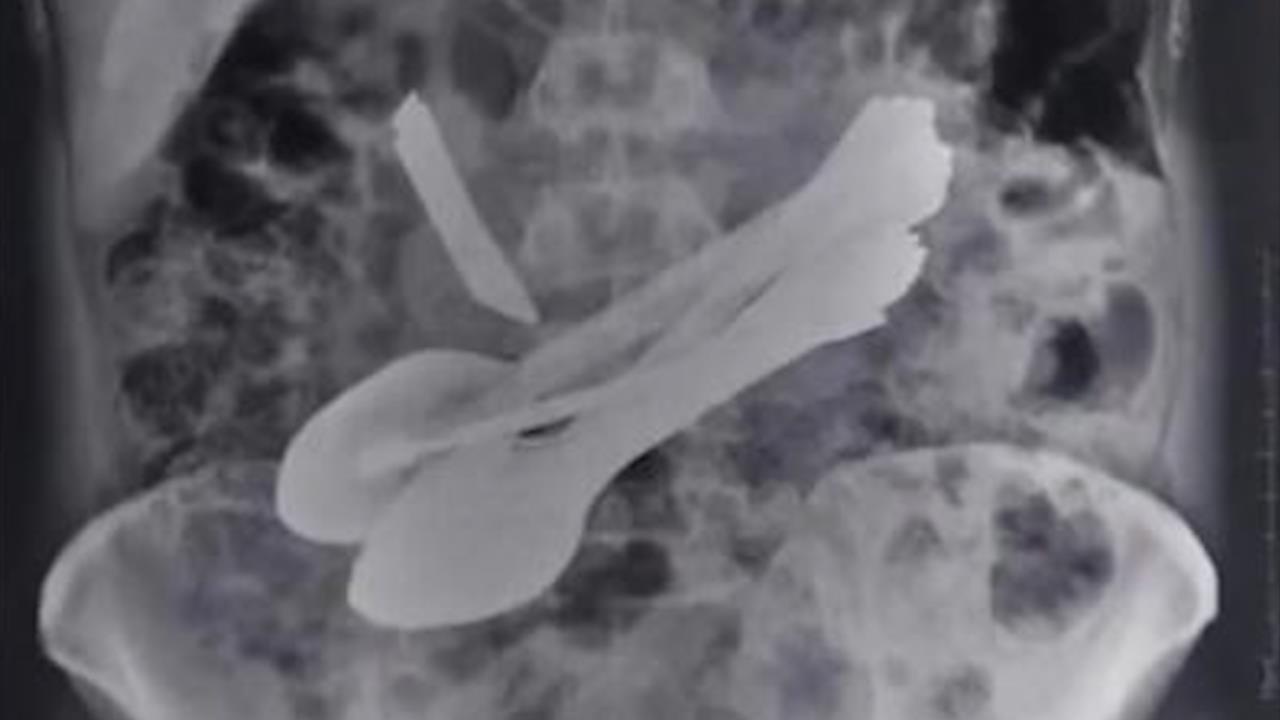

Một người đàn ông Ấn Độ phải nhập viện vì cơn đau bụng dữ dội sau khi bác sĩ thăm khám và phát hiện trong bụng anh này có đến một tá bàn chải, thìa, dao và dĩa.

Trong quá trình tự sơ cứu hóc xương cá, bệnh nhân dùng bàn chải đánh răng để lấy ra, không may nuốt luôn vào trong dạ dày.